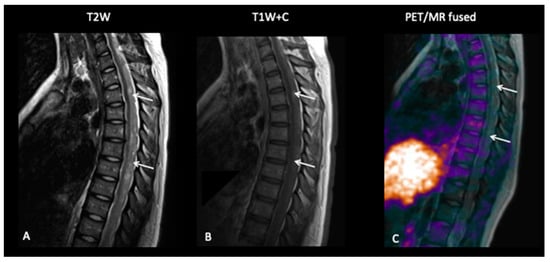

- Patient 10: Diagnosis

This 15-year-old female had a short-presenting history of recurrent headaches, vertigo, back ache and a band like numbness around the right breast and chest. She also complained of her legs “giving away”. MRI of the brain and spine revealed multiple lesions involving the brain with multiple drop spinal lesions occupying the spinal canal, compressing the spinal cord and nerve roots at all the levels (Figure 13), suggestive of a high-grade tumour. Surprisingly, the FCho PET–MRI showed that all the lesions in the brain and spine were choline non-avid, suggestive of a low-grade tumour, i.e., a low proliferative index, but a subsequent biopsy of the spinal lesion confirmed medulloblastoma.

Figure 13.

Spinal MRI (A,B) demonstrates extensive intraspinal-enhancing soft tissue in keeping with leptomeningeal metastatic disease (arrows point out the leptomeningeal disease). However, the FCho PET (C) did not demonstrate avidity of the leptomeningeal disease (arrows).